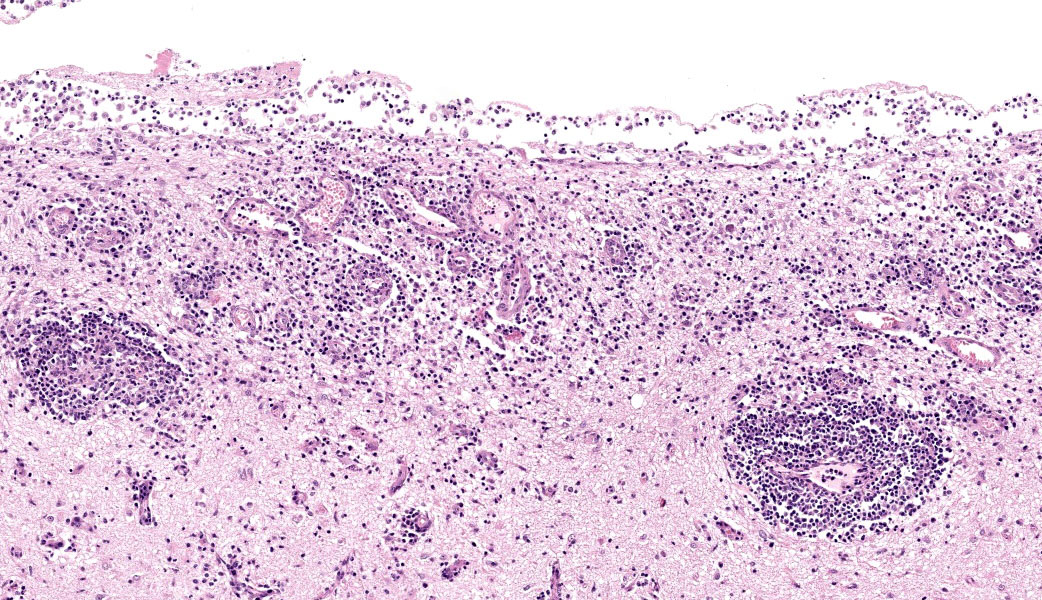

Brain: The meninges are moderately expanded by macrophages, plasma cells, and lymphocytes that surround and partially obscure reactive meningeal vessels. Inflammatory cells extend around vessels into the subtending parenchyma, filling and expanding Virchow Robin spaces up to 12-15 cell layers thick. There are focal areas of infiltration of macrophages, lymphocytes, and plasma cells into the surrounding parenchyma with associated vacuolation and necrosis of the parenchyma, neuronal satellitosis and necrosis, infiltration of gitter cells, gliosis, and astrocytosis. Isolated within the parenchyma and associated with areas of inflammation and necrosis are numerous 12 to 45-µm diameter protozoal cysts containing closely packed clusters of 1 to 2-µm wide, crescent-shaped bradyzoites. At the level of the corpus striatum, there is vacuolation of white matter tracts with occasional spheroids, digestion chambers, and numerous protozoa. Vessels adjacent to the lateral ventricle are obscured by macrophages, lymphocytes, plasma cells, and neutrophils with indistinct, hypereosinophilic vascular walls (necrosis) and perivascular exudation of fibrin and edema. The ependyma spanning the lateral ventricle is segmentally discontinuous with disruption by inflammatory cells and necrotic material that extend into the ventricular lumen.

Brain: Meningoencephalitis and ventriculitis, necrotizing and histiocytic to lymphoplasmacytic, subacute, multifocal, moderate, with protozoal cysts and zoites, vasculitis and vascular necrosis.

Cerebrum: Meningoencephalitis, necrotizing and lymphohistiocytic, subacute, multifocal to coalescing, marked, with vasculitis and apicomplexan cysts.